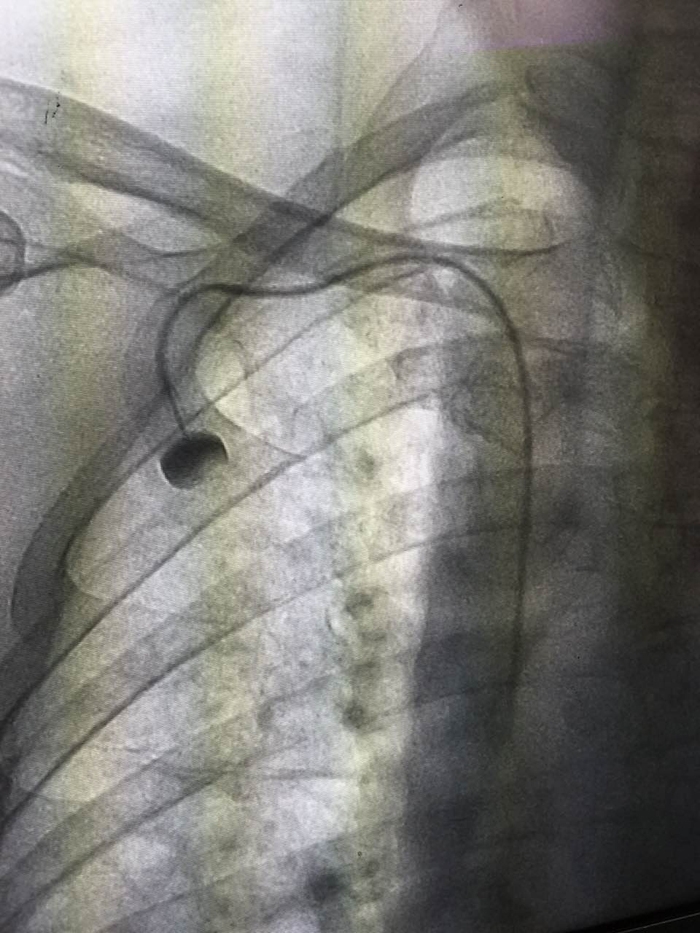

“靜脈輸液港”的X影像

??? PORT(輸液港)是一種較新的輸液管路技術(shù),是埋植于人體內(nèi)的閉合輸液系統(tǒng),主要由供穿刺的注射座和靜脈導(dǎo)管系統(tǒng)組成。利用小手術(shù)方法將導(dǎo)管經(jīng)皮下穿刺置于人體大靜脈中,如鎖骨下靜脈、上腔靜脈,部分導(dǎo)管埋藏在皮下組織,將另一端的穿刺座留置在胸壁皮下組織中并縫合固定,手術(shù)后皮膚外觀只看到一個(gè)小的縫合傷口,愈合拆線后病人體表可觸摸到一突出圓球。治療時(shí)將針經(jīng)皮穿刺垂直進(jìn)入到穿刺座的儲(chǔ)液槽,既可以方便地進(jìn)行注射,也可以長(zhǎng)時(shí)間連續(xù)輸液和采血,而且適用于高濃度的化療藥物、完全胃腸外營(yíng)養(yǎng)、血液制品的輸注。輸液港植入后病人的日常生活不受限制,接受藥物治療方便又輕松,可在人體內(nèi)存留使用5年甚至更長(zhǎng)的時(shí)間。這種技術(shù)的應(yīng)用對(duì)白血病患者、惡性腫瘤患者以及長(zhǎng)期需要打針輸液的重癥患者,尤其是此類疾病的兒童患者來說,有著重要的意義。